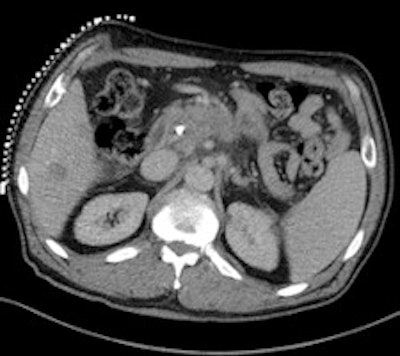

A 50-year-old man with history of pancreatic carcinoma underwent a CT-guided biopsy (above), which was nonconclusive (pathology result: normal liver tissue). Three weeks later, an MR-guided biopsy (below) was performed, and the biopsy revealed a cavernous hemangioma. Images courtesy of Dr. Rüdiger Hoffmann.